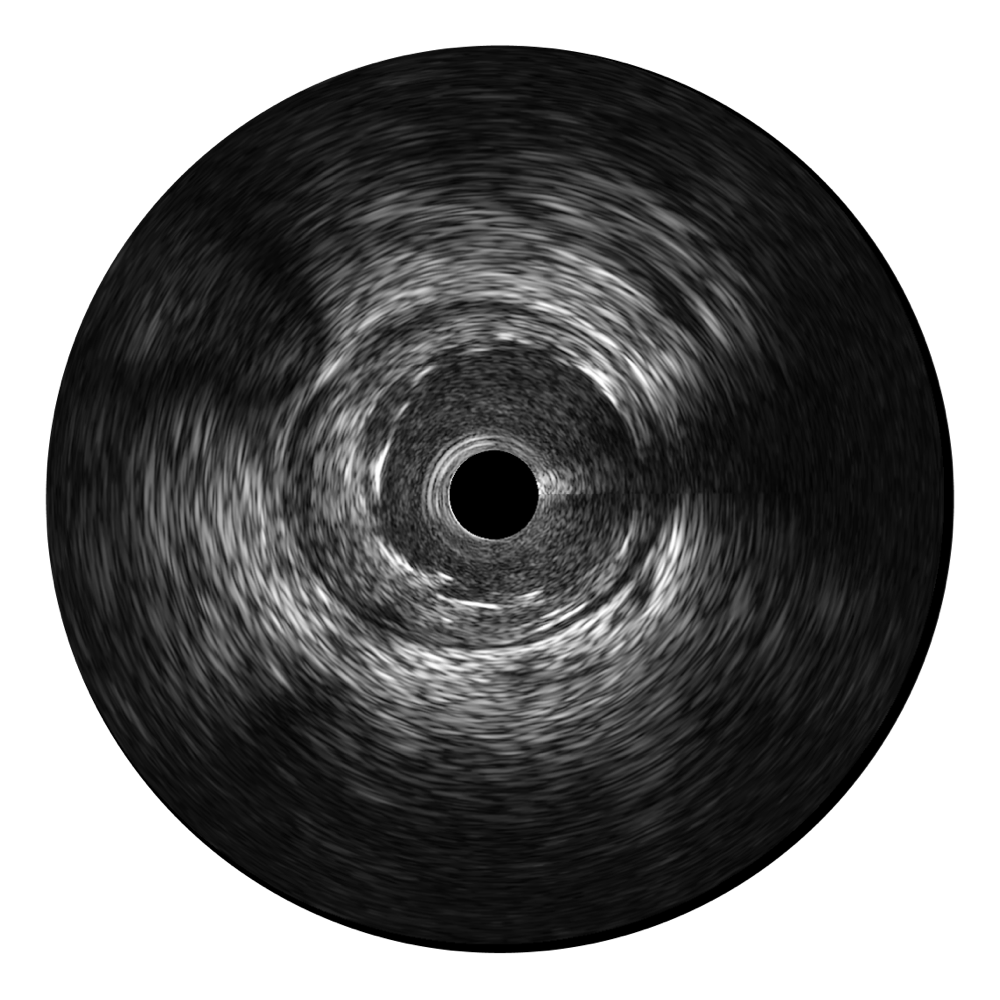

• 哈哈体育官网宽频IVUS图像

对比传统IVUS导管成像,哈哈体育官网宽频IVUS图像的近场支架梁显影更细腻,远场中膜外血管仍清晰可辨,兼顾远中近,兼顾分辨力与穿透深度